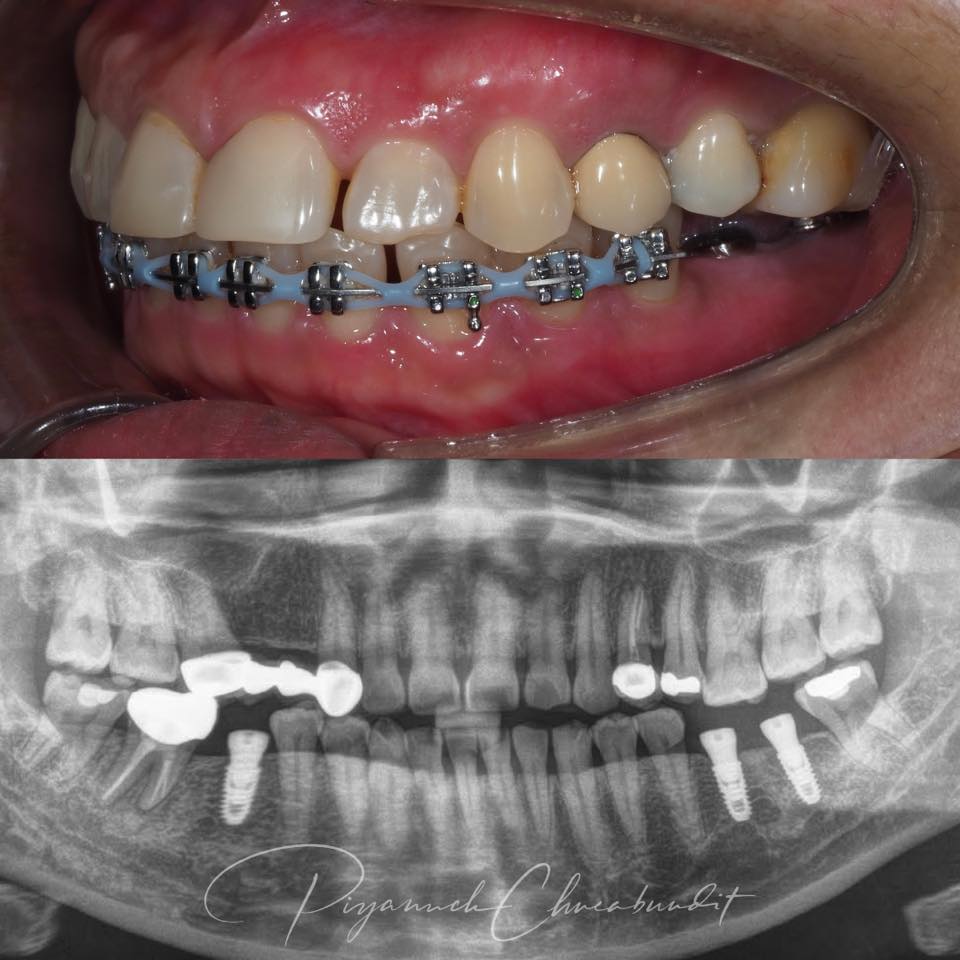

ประเภทรากเทียม (Dental Implant)

1.Single Implant (รากเทียมเดี่ยว)

สำหรับใช้แทน ฟันที่หาย 1 ซี่ ใส่รากเทียม 1 ตัว + ครอบฟัน 1 ซี่

2.Bridge on Implant (สะพานฟันบนรากเทียม)

เหมาะกับผู้ที่มีปัญหาฟันหาย หลายซี่ติดกัน จะใช้รากเทียม 2 ตัว รองรับฟัน 3–4 ซี่

3. All-on-X (All-on-4 / All-on-6)

คือการติดฟันปลอมทั้งขากรรไกร โดยการยึดด้วยรากเทียม จะใช้รากเทียม 4 หรือ 6 ตัวรองรับฟันทั้งขากรรไกร (บนหรือ ล่าง) เหมาะกับ ผู้ที่มีปัญหาฟันหายทั้งปาก หรือมีฟันเหลืออยู่แต่ใช้งานไม่ได้ คนไม่อยากใส่ฟันปลอมถอดได้